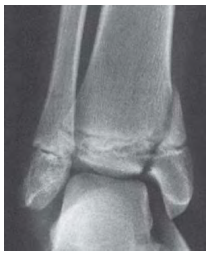

Um paciente adolescente apresentou entorse grave de tornozelo há uma hora, sendo levado ao atendimento em cadeira de rodas por incapacidade de deambular. Apresentava, ao exame físico, dor bimaleolar importante. Foi realizada a radiografia mostrada na imagem.

Com base nesse caso clínico, é correto classificar essa lesão como Salter-Harris tipo